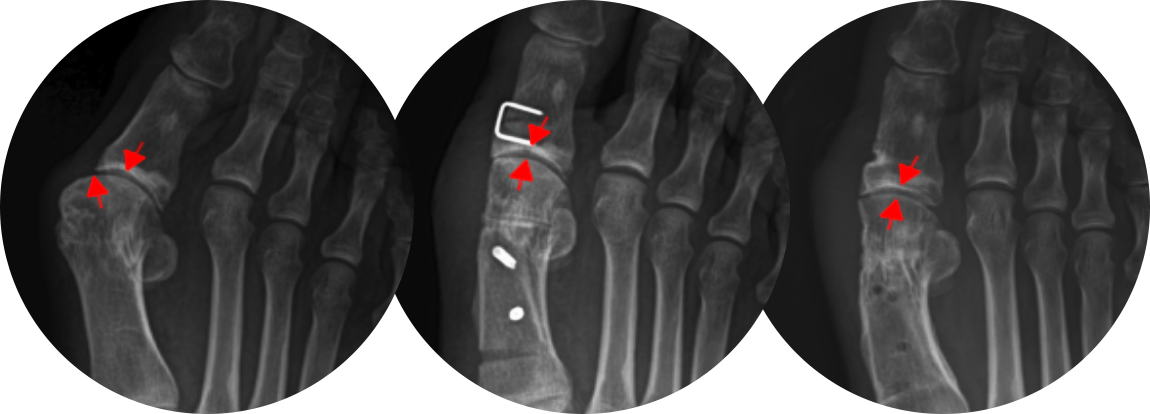

첫번째 사진을 보면 중족골두에서 근위지골의 기저부가 완전히 벗어나 있는 것을 확인할 수 있고,

수술 후에는 관절이 잘 맞아 들어간 것을 확인할 수 있습니다.

근위 중족골 절골술과 스카프 절골술의 경우 교정력이 좋기 때문에 주로 중증 무지외반증에 적용합니다.

개방형 원위 절골술의 경우 절골 방법은 MICA 와 비슷하지만 조금 더 안정적이고 절개가 크지 않으면서

연부조직의 처리가 같이 가능하기 때문에 필요한 경우 적용할 수 있습니다.

절개 수술법의 경우 큰 각도의 변형을 교정할 수 있습니다.